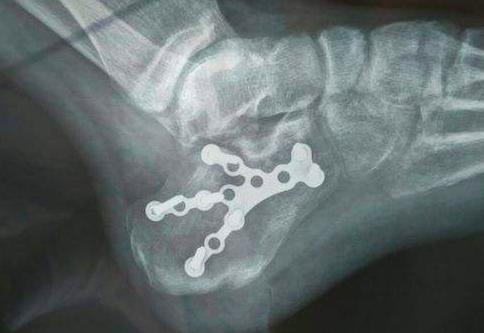

骨折严重者,需要经过手术钢板固定,将碎成几块的骨头,『拼合』起来固定。跟骨骨折的复位要求较高,要恢复关节与各关节面间的正常解剖关系(就是各归各位,保持正确的间距),同时,满足负重力线的种种要求。这样才能最大限度地减少创伤性关节炎的发生。

手术治疗:骨折移位明显,波及关节面的骨折,保守治疗无法达到良好愈合的情况。手术通过可以通过克氏针撬拨复位及钢板固定,有利于恢复跟骨高度及各关节面的角度。当然,手术策略及入路的选择多如牛毛,比如Sanders分型就有IV型,还有AO 及Essex-Lopresti分型等。这里不作具体讨论。

有点像把摔碎的鸡蛋壳,给缝起来。